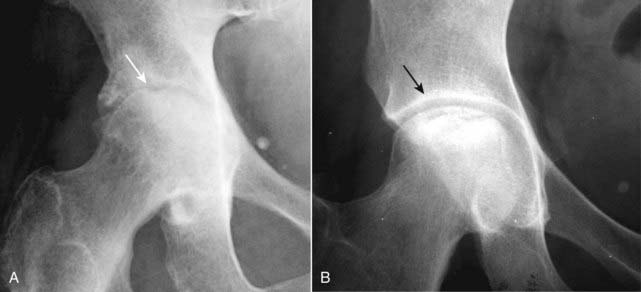

Figure 23-2 Arthritis or not?

An arthritis is a disease that affects a joint and usually the bones on either side of the joint, almost always accompanied by joint space narrowing. A, This disease meets those specifications. There is narrowing of the hip joint, and both the femoral head and the acetabulum are abnormal (solid white arrow). This is osteoarthritis of the hip. B, There is an abnormality of the femoral head (sclerosis) but the joint space is normal as is the acetabulum (solid black arrow). This is avascular necrosis of the femoral head.